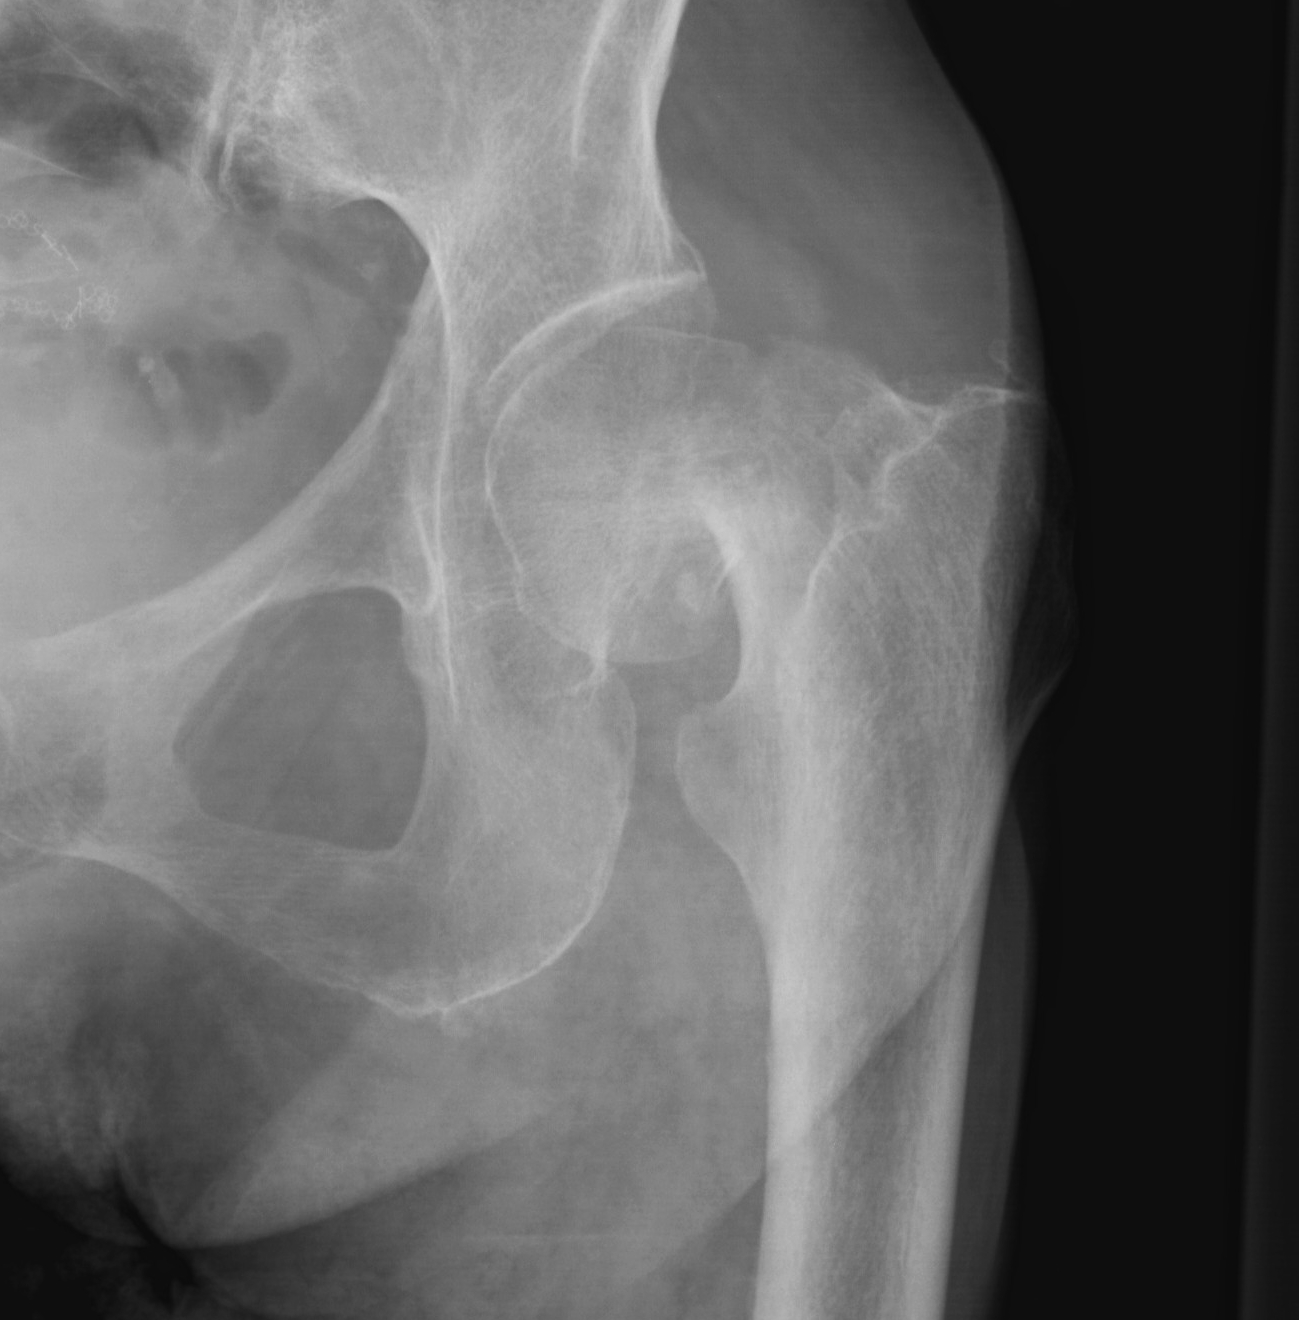

Type I: Incomplete, valgus impacted fracture

Type II: Complete fracture, undisplaced

Type III: Complete fracture, partial displaced, trabeculae don't line up with acetabulum

Type IV: Complete fracture, completely displaced, trabeculae line up with acetabulum

Garden's Classification

| Garden | Description | Displacement |

| I |

Incomplete Valgus impacted Lateral cortex fractured Medial cortex intact |

Undisplaced |

| II | Complete | Undisplaced |

| III |

Complete fracture Partial displacement Trabeculae don't line up with acetabulum |

Displaced |

| IV |

Complete fracture Complete displacement Trabeculae line up with acetabulum |